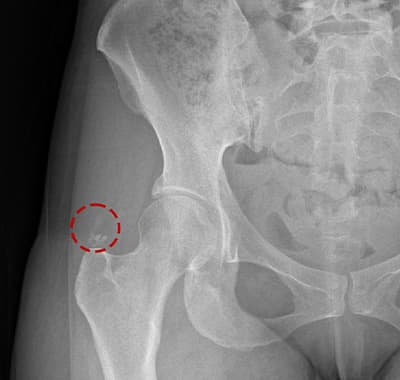

시술 전후 X-ray — 실제 케이스

단단한 석회도 1회 시술 후 완전 제거. 실제 환자 X-ray입니다.

케이스 1 — 시술 전·후

케이스 2 — 시술 전·후

케이스 3 — 시술 전·후